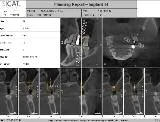

In addition, the introduction of office-based cone beam volumetric tomographic (CBVT) machines in 1999 came together with the advances in surgical planning software. This software comes either as a third party or as native to the image acquisition and viewing software included with the imaging hardware and has made implant therapy predictable and accurate (Fig. 2).

CBVT machines and surgical planning software

Computer-based implant planning and placement allows for creation of an exact replica of the jawbone on the computer screen, allowing visualization of all the vital structures such as nerves, sinuses, nasal floor, proximal teeth and concavities like the one below the mylohyoid ridge in the posterior mandible (Figs. 8a, b). Thus, practitioners can safely avoid these structures when planning and ultimately placing the implants using CAD/CAM generated surgical guides (Figs. 9–11).

Jawbone replica Jawbone replica